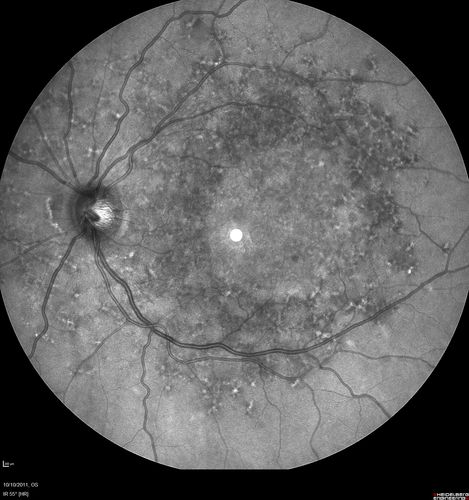

Stargardt's Macular Dystrophy ABCA4 positive

Images show some progression over 3 years of macular dystrophy.

Stargardt's Macular Dystrophy - Heterozygous ABCA4 T>C substitution at potisoin -10 of intro 38